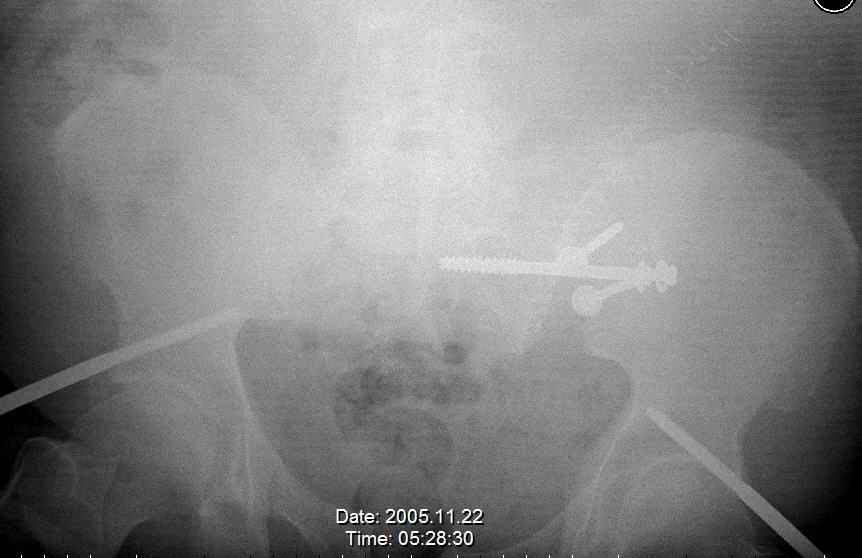

Was hemodynamic unstable at local ER, sent to our Trauma center where circumferential pelvic binder placed and pt. stabilized with fluid, blood, and rewarming. Angiography not performed. An extraperitoneal bladder disruption was found, uro elected to treat non-operatively. Initial xray (not shown) demonstrated 5-7 cm wide at symphysis and SI joint. The first image attached is of CT once binder is in place.

On post trauma day 5 the pt was taken to OR for ORIF of his iliac wing fracture and SI dislocation. The swelling/3rd spacing of fluid in the area of symphysis was profound, but quite acceptable posteriorly.

Patient was prone for procedure, as I thought too difficult to fix the wing in lateral position. Of course the repair of wing was easy, but reduction of SI very demanding. The Floro images document the residual lack of reduction. That was the closest I could get it using 6mm joystick in wing, and clamp on sacrum and clamp through notch. The fixation was (initially) rigid. Anterior ex fix with supra-acetabular pins was placed due to condition of soft tissues, massive "beer-belly" overhanging the crest.